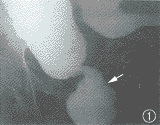

结肠钡剂造影:乙状结肠右位,其下段肠管呈环形狭窄并可见多个类圆形充盈缺损,狭窄近段肠管明显扩张(图1),侧位示骶前间隙增宽达4.5 cm。

图1 钡灌肠示右位乙状结肠,其与直肠交界部环行狭窄并见数个类圆形充盈缺损,近段肠管扩张